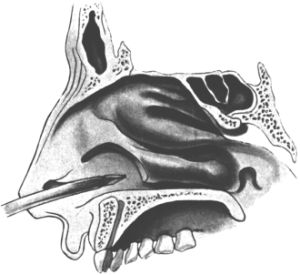

| 210. | Passing the Eustachian Catheter | 365 |

| 211. | Passing the Eustachian Catheter | 365 |

| 212. | Passing the Eustachian Catheter | 366 |

| 213. | Passing the Eustachian Catheter | 366 |